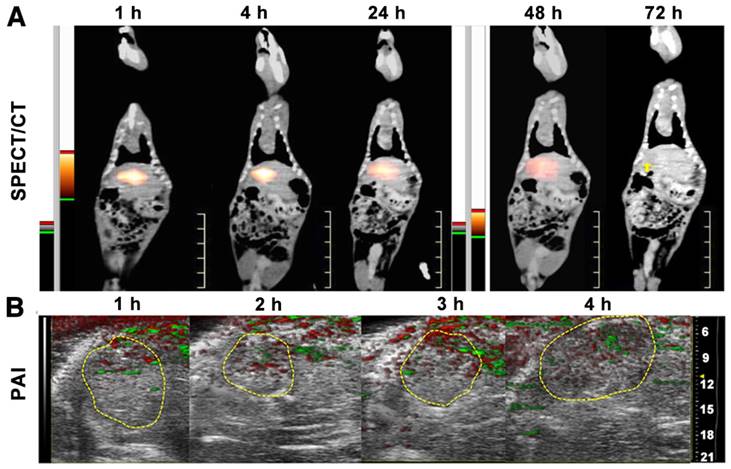

SPECT/CT and photoacoustic imaging

SPECT/CT imaging provided the whole-body distribution of 131I-HCuSNPs-MS-PTX post IA injection of 131I-HCuSNPs-MS-PTX (Figure 9A). 131I-HCuSNPs-MS-PTX was mainly found in the liver tumor and there was minimal uptake in the rest of the organs, in particular the lungs. Moreover, the SPECT/CT scanning confirmed that the 131I stayed in tumors for 48 h following the IA administration (Figure 9A). From the photoacoustic images, the microsphere distribution in the tumor had photoacoustic signal intensities of 0.058 a.u., 0.048 a.u., 0.064 a.u. and 0.077 a.u. at 1 h, 2 h, 3 h and 4 h post-injection, respectively (Figure 9B).

Figure 9

A, SPECT/CT scans of tumor-bearing rats after IA injection of 131I-HCuSNPs-MS-PTX (80 μL, 10 mg, containing 0.5 mg of PTX, 0.58 × 1011 of HCuSNPs and 28 MBq of 131I) showed that tracer uptake localized to the hepatic tumor (yellow arrow indicates site of tumor). B, Photoacoustic imaging (PAI) of liver in the tumor-bearing rats after IA injection of 131I-HCuSNPs-MS-PTX (80 μL, 10 mg, containing 0.5 mg of PTX, 0.58 × 1011 of HCuSNPs and 28 MBq of 131I). Green indicates photoacoustic signals of 131I-HCuSNPs-MS-PTX; red reflects photoacoustic signal of hemoglobin.